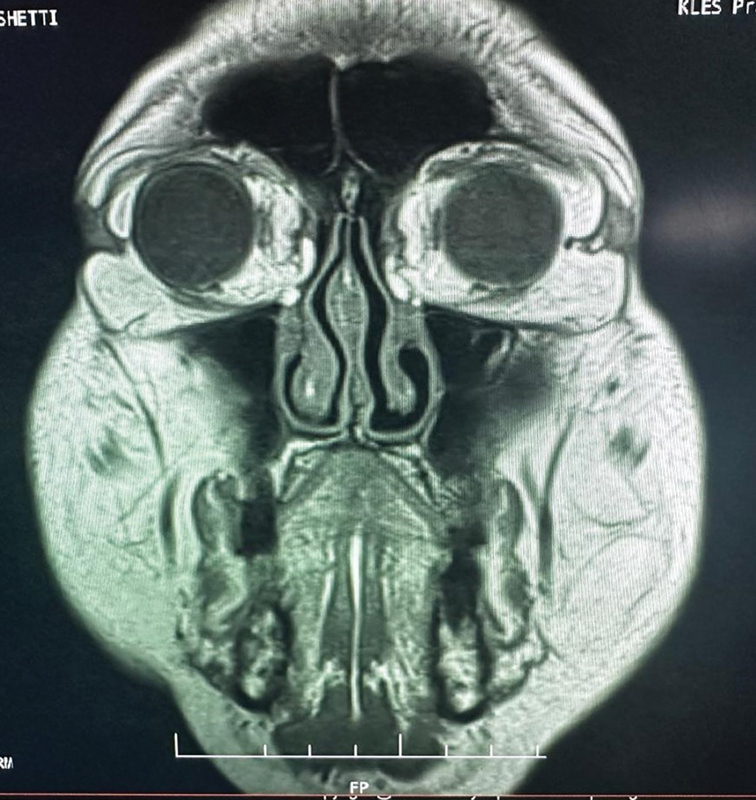

Subconjunctival orbital fat prolapse is a benign condition where the orbital fat, which normally cushions the eye within its socket, protrudes or herniates through the conjunctiva, the clear membrane covering the sclera. It is a rare condition that occurs due to disruption of the orbital septum due to various causes. In this case study, we report the clinical findings, treatment, and insights gained from the diagnosis and management of a 59-year-old male patient with subconjunctival orbital fat prolapse.

Abstract Image